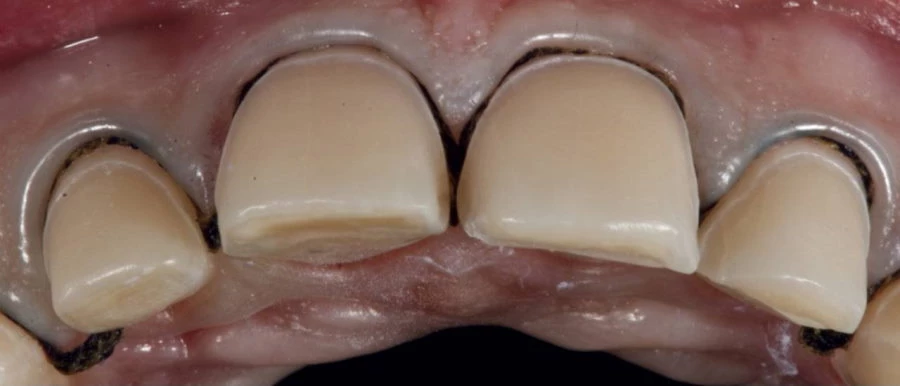

它们的最大优点是,在制作完成后不会像使用金属陶瓷牙冠那样在牙龈边缘出现灰线。其原因是陶瓷贴面是由一种无金属材料制成的。

贴面陶瓷就像牙齿本身的组织一样,是半透明的,光线照射下是透明的。有了这个特点,可以达到极高的美学效果,所以我们几乎无法分辨我们看到的是病人自己的牙齿还是贴面的陶瓷修复体。

在牙科美容干预过程中,我们实践中的贴面由IPS e.max®压制陶瓷制成,这使我们能够获得有足够抵抗力、高精确度和美观的最终结果。